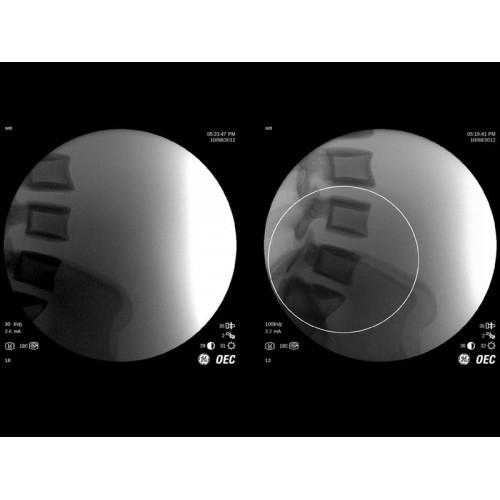

GE Brivo OEC 785/865 оснащен инновационной системой обработки изображений, которая обеспечивает четкую визуализацию в реальном времени. Система автоматически адаптирует параметры исследования под конкретную хирургическую задачу, обеспечивая оптимальное соотношение качества изображения и лучевой нагрузки. Особое внимание уделено эргономике работы хирургической бригады.